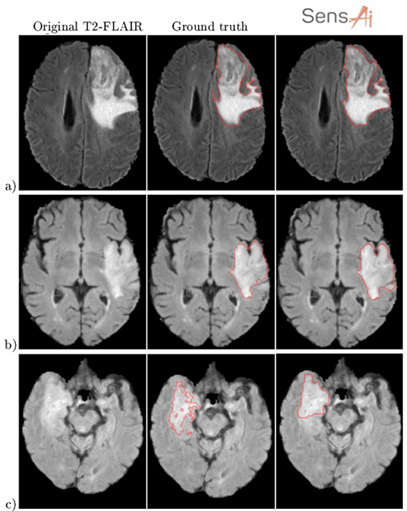

We’ve been driving down this very route with Sens.AI – the automated tool for segmenting low- and high-grade gliomas from FLAIR MRI. Such software must be CE-marked to be deployable in clinical settings (or FDA-cleared in the US). You must manage the risk, prepare documentation, and validate it. We can’t just throw any data at the algorithm! For training to work, we need high-quality examples that effectively teach the algorithm how to operate. The heart of Sens.AI is the U-Net-based deep neural network – this architecture is used for both brain extraction (the process of removing the skull from input FLAIR MRI images), and for delineating tumors. After training and setting up the processing system, we can test it on new data, like scans from your local hospital. Here’s hoping it works like a charm! (Fig. 4). Can you quantify our hopes though?

Figure 4 [6].

We tackled those issues by combining quantitative, qualitative, and statistical analysis in our validation process. On the one hand, we calculated and analyzed classical quality metrics. Moreover, we performed the mean opinion score (MOS) experiment. Firstly, we segmented the test MRIs (never used for training) using Sens.AI. Then we asked the experienced readers to assess the segmentations. There were just four options, ranging from “Very low quality, I would not use it to support diagnosis”, to “Very high-quality segmentation, I would definitely use it”. Readers evaluated the segmentations without knowing where they came from (blinded setting). Moreover, each reader scored each segmentation once. Disagreements are sure, right? Lastly, the visual assessment isn’t an easy task. Are jagged contours worse than the smooth ones? Shall we include more hyperintense tissue in the tumor region? Quite a number of open questions here (Fig. 5).

Figure 5 [6]